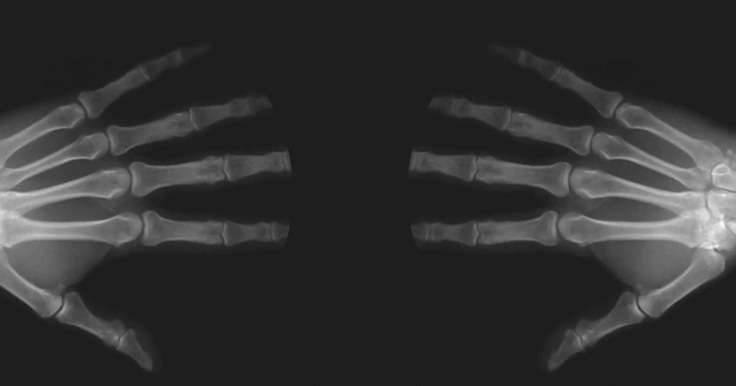

▼从这个核磁共振影像中,可以清楚看到折手指时关节之间产生的变化,关节空隙被拉大,中间润滑的关节液被拉长,因此使里头的气体释放出来。